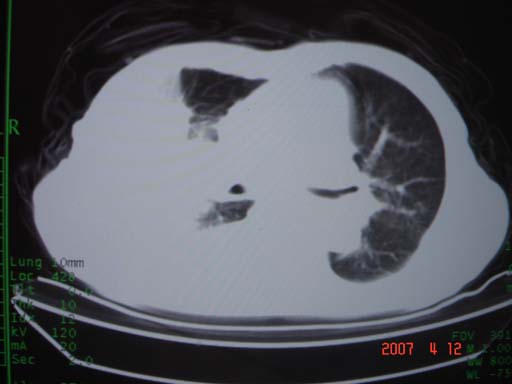

帮我 看看。男77岁咳嗽咯血2月发热2周!病人一般情况可 口痰为鲜红,有点象洗肉水(我看见他吐的痰了)

为何只有这么几幅图像?连纵隔窗都没有。但我发现上叶支气管显示不清,再加上年纪大,咯血等症状,恶性肿瘤首先得考虑。

考虑右肺新生物伴右中上肺阻塞性肺炎及含气不良,右侧胸腔积液。建议痰与纤支镜检查

考虑右侧中央型肺癌伴中上肺阻塞性肺炎、不张,胸腔积液。,建议支纤镜检查。

考虑:右上肺癌伴中上叶炎症,右侧胸腔积液。

图片不太全

根据患者老年男性,右肺上叶支气管狭窄、阻塞,伴阻塞性肺炎,考虑中心型肺癌可能性大。建议支气管镜检查

病灶局限在右肺中上叶,呈大片状实变影,内见空气支气管征,支气管分支较柔软,纵隔内未见肿大淋巴结.支持:感染性病变_1 大叶性肺炎.2 干酪性肺炎.

优先考虑右上肺干酪性肺炎并同侧中叶播散、胸腔积液。分析:右膈肌未见升高、纵隔未见明显右移,胸部各组淋巴结未见可疑肿大,中叶可见支气管铸形,肺野、肺门未见可确定肿块。

右肺上叶后段支气管中断,首先考虑中央型肺癌并右肺不张及纵隔淋巴结转移,右侧胸腔积液。

右肺上叶实变,实变范围如此之大,如果用肺癌解释的化,应该是比较大的支气管开口发生完全阻塞,但观察上叶前后段支气管还是比较通畅,所以应考虑感染性病变,大叶性肺炎可能,建议抗炎治疗后复查。